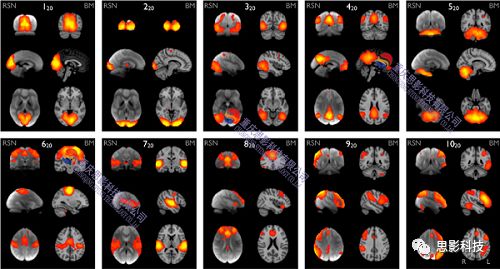

5)基于ICA的腦網(wǎng)絡分析

通過盲源分離算法,在組水平上計算出時間上相互獨立的體素集合,來找出具有功能一致性的大腦區(qū)域,以此界定不同的腦功能網(wǎng)絡。